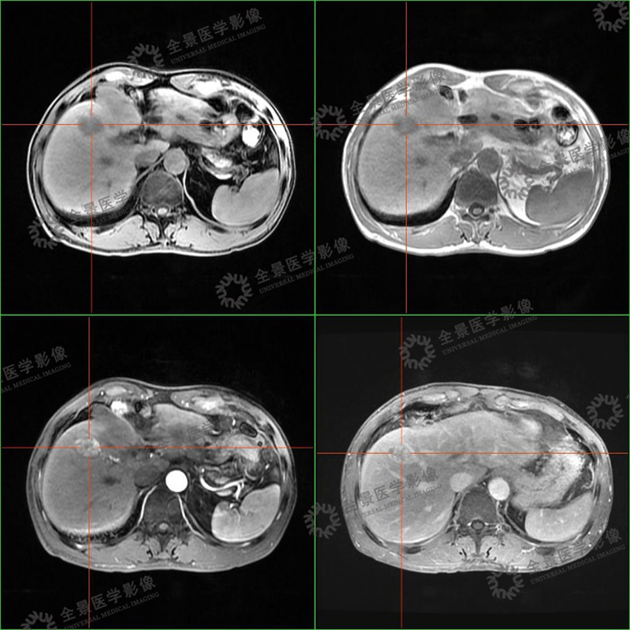

案例1 :中年男性,公司体检报告中超声提示肝右叶稍高回声影,结合今年突然消瘦了十几斤,行MR(磁共振)上腹部增强扫描:

表现:肝S5段团片影,增强扫描持续强化。考虑有肿瘤可能性,但无法明确。由于当天肝脏肿瘤指标AFP结果未出,结合已做的腹部彩超和MR增强扫描,考虑肿瘤可能性大。

医生建议他进行全面的PET/CT检查。

PET/CT图像

PET/CT-MR异机融合图像

实验室检查:乙肝阳性,肿瘤标志物:AFP 800+。

结合实验室检查,诊断为肝癌。

目前患者肝癌已切除,术后病理也已证实。

表现:CT显示不清,行PET/CT-MR融合检查,MRI显示清晰,PET提示病灶有轻度FDG摄取,诊断为小肝癌。